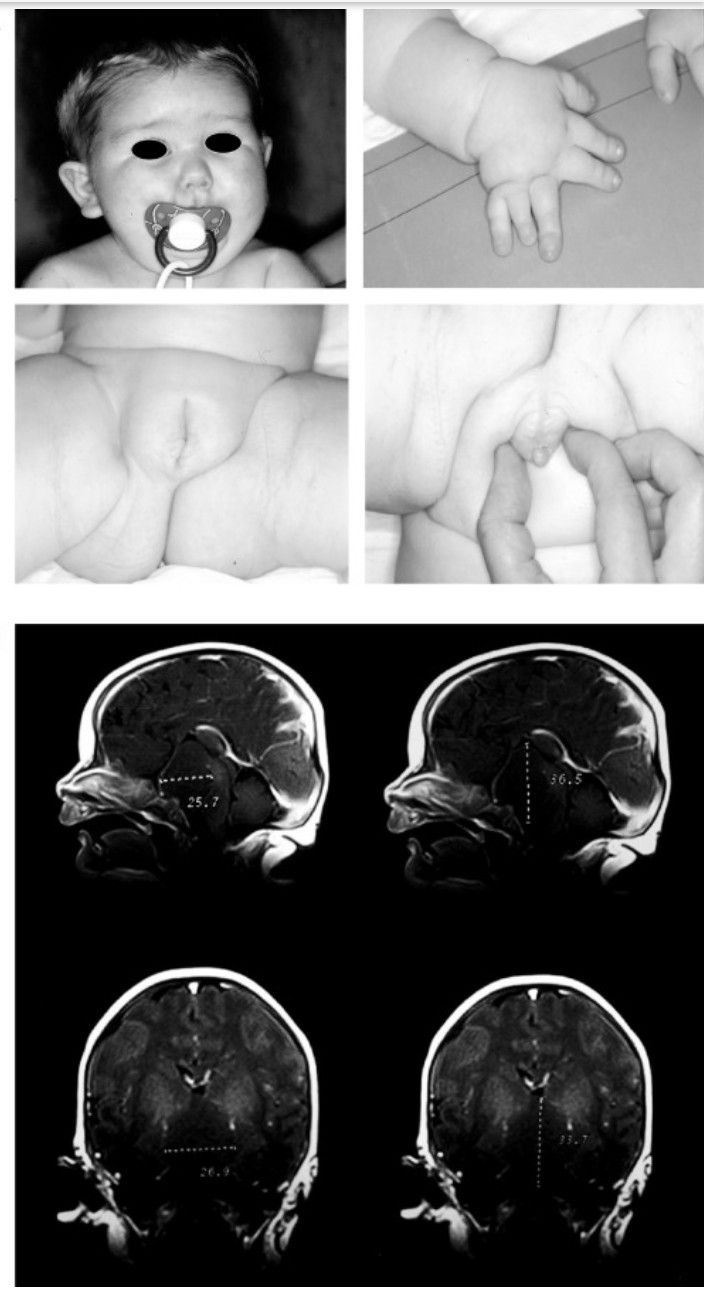

Pallister-Hall syndrome is a genetic disorder. The gene encoding the zinc finger transcriptional activator protein on chromosome 7p14.1 is mutated. This mutation results in hyperplasia of neurons admixed with astrocytes and decreased white matter. In addition, hypothalamic hamartomas on floor of the third ventricle are the characteristic finding. The individual with Pallister-Hall syndrome presents with: - Endocrine abnormalities - Bifid epiglottis - Atretic anus - Renal disorders - Genitourinary anomalies - Limb malformation - Craniofacial abnormalities - Pulmonary segmentation anomalies The prognosis depends on the severity of malformations. In case of severe airway malformation, laryngotracheal clefts, and panhypopitutarism, the prognosis is worse. Reference: https://radiopaedia.org/articles/pallister-hall-syndrome?lang=us Image via: https://www.sciencedirect.com/topics/nursing-and-health-professions/pallister-hall-syndrome